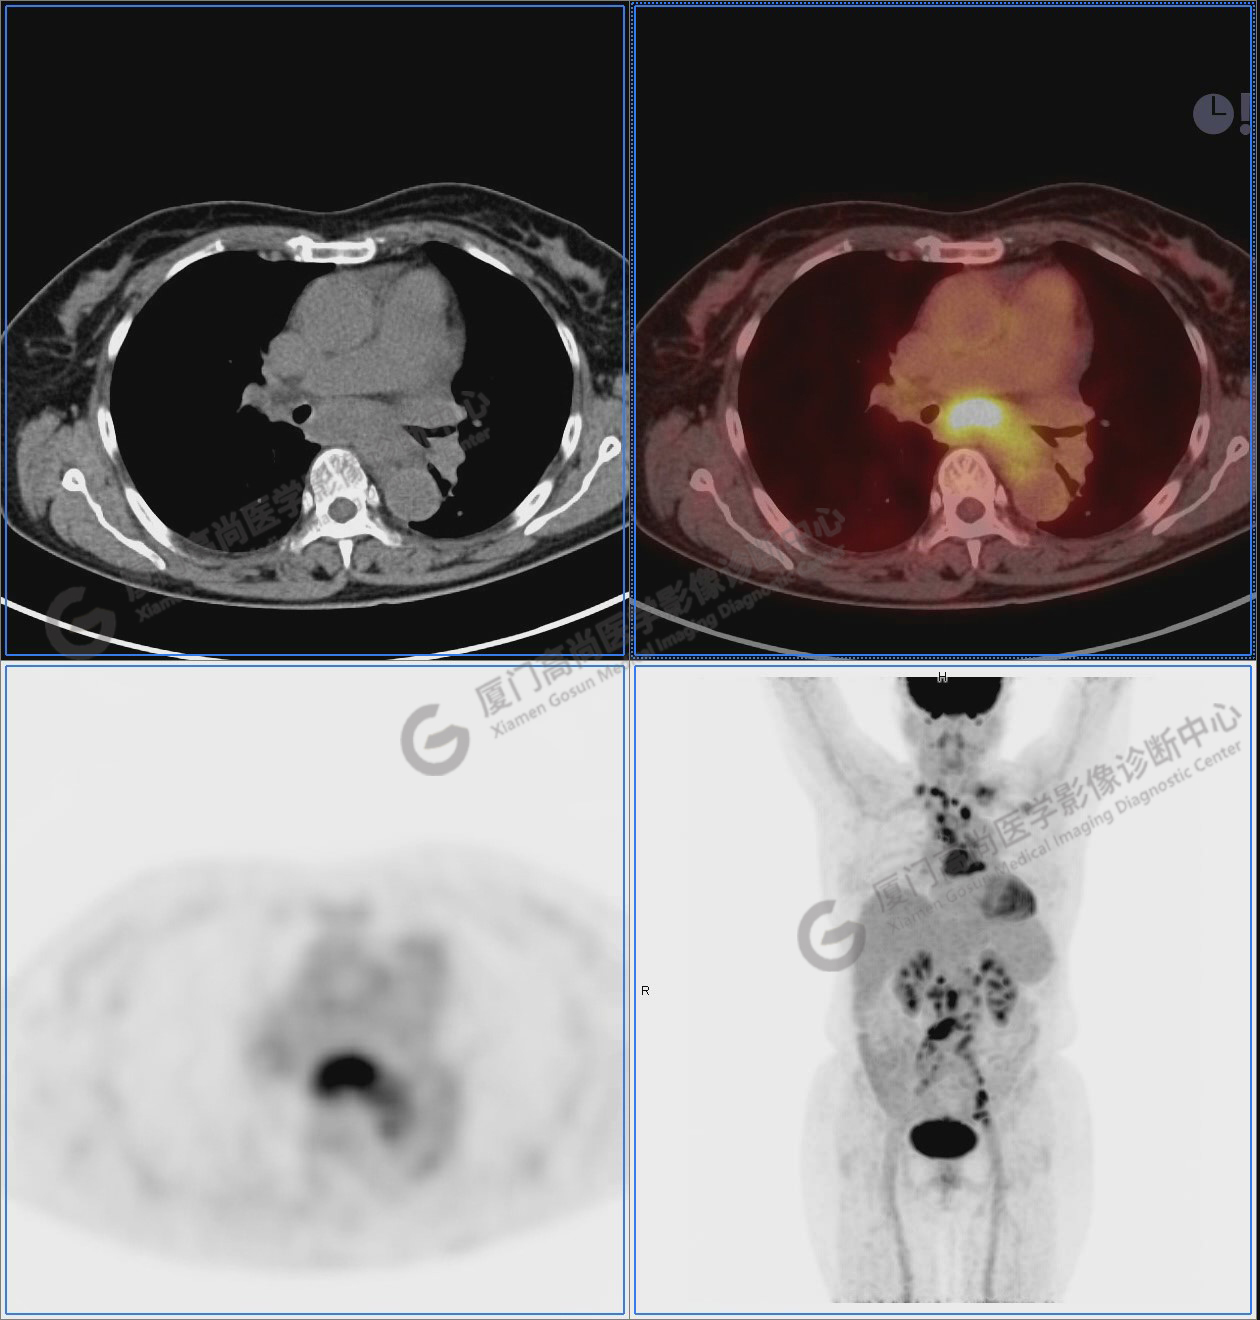

圖10-11:子宮頸軟組織腫塊,代謝異常增高,考慮為宮頸癌。

圖10

圖12-13:延遲2小時后,宮頸腫塊糖代謝進一步增高。

圖12